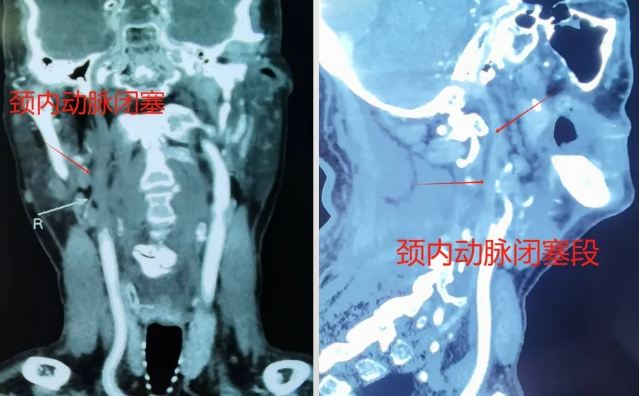

为确保手术成功,姜昊主任医师特邀神经外科邵斌主任、麻醉科、介入导管室等多个学科进行深入讨论,完善各项检查,共同制定手术方案,并对术中可能发生的各种突发情况均准备了应急预案。脑血管造影很快结束,确定了姜老先生是因右侧颈动脉闭塞导致了一系列症状。姜昊主任详细评估并与患者家属充分沟通后,决定为姜老先生行颈动脉慢性闭塞介入再通术。术中麻醉科和介入导管室严格监测患者各项生命体征,ICU随时待命为姜老先生保驾护航。各个学科的通力合作为手术的成功奠定了坚实的基础。